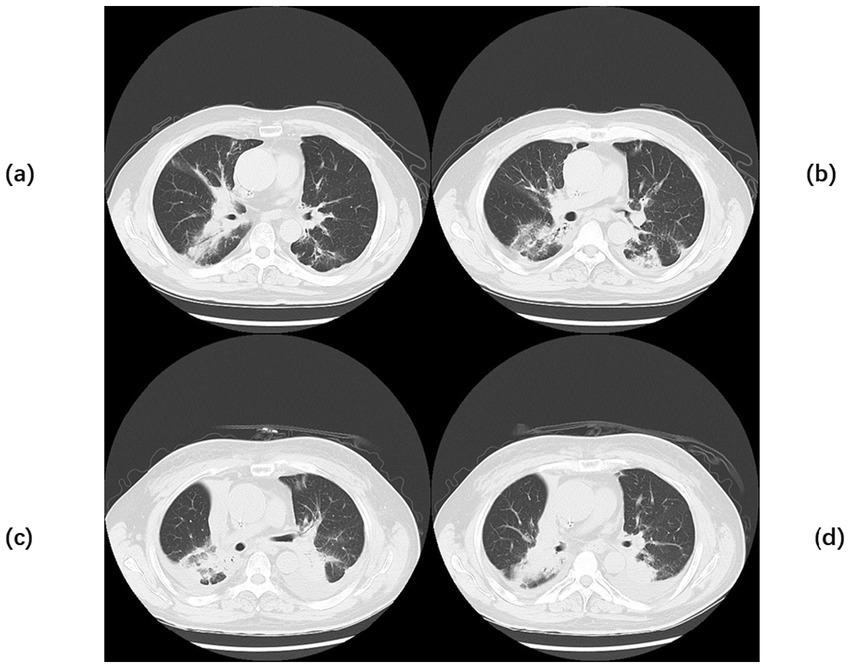

Figure 3

Chest CT of Case 2. Computed tomography (CT) of the chest before the start of treatment (a,b) large, patchy high-density foci under the pleura of the right lung with blurred margins and uneven density. Chest CT after 2 months of continuous treatment (c,d) Flocculent and patchy slightly high-density foci were seen under the pleura of the lower lobe of the right lung, with fuzzy edges and uneven densities, which were significantly better than before.